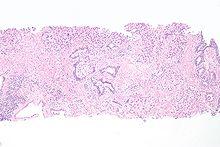

Micrograph of urethral cancer (urothelial cell carcinoma), a rare problem of the urethra.

Cancer can also develop in the lining of the urethra.[19] When cancer is present, the most common symptom in an affected person is blood in the urine; a physical medical examination may be otherwise normal, except in late disease.[19] Cancer of the urethra is most often due to cancer of the cells lining the urethra, called transitional cell carcinoma, although it can more rarely occur as a squamous cell carcinoma if the type of cells lining the urethra have changed, such as due to a chronic schistosomiasis infection.[19] Investigations performed usually include collecting a sample of urine for an inspection for malignant cells under a microscope, called cytology, as well as examination with a flexible camera through the urethra, called urethroscopy. If a malignancy is found, a biopsy will be taken, and a CT scan will be performed of other body parts (a CT scan of the chest, abdomen and pelvis) to look for additional metastatic lesions.[19] After the cancer is staged, treatment may involve chemotherapy.